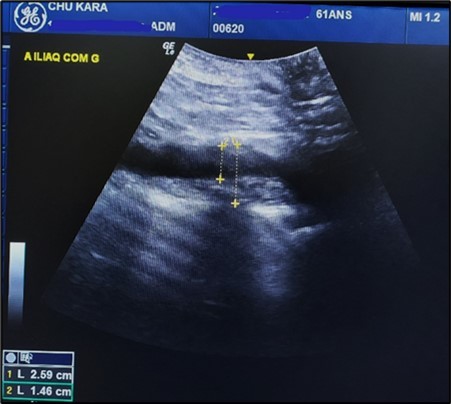

The aneurysms had extensions to other arteries in 21 patients (65.63%) distributed as follows: superior mesenteric artery (11.76%) (Figure 3) and (Figure 4), celiac trunk (14.23%), iliac arteries (57.14%) femoral arteries (19.05%). (Figure 5) and (Figure 6)

Figure 6.AAA extension with extension to the common iliac artery in a 61-year-old patient (CHU-Kara)